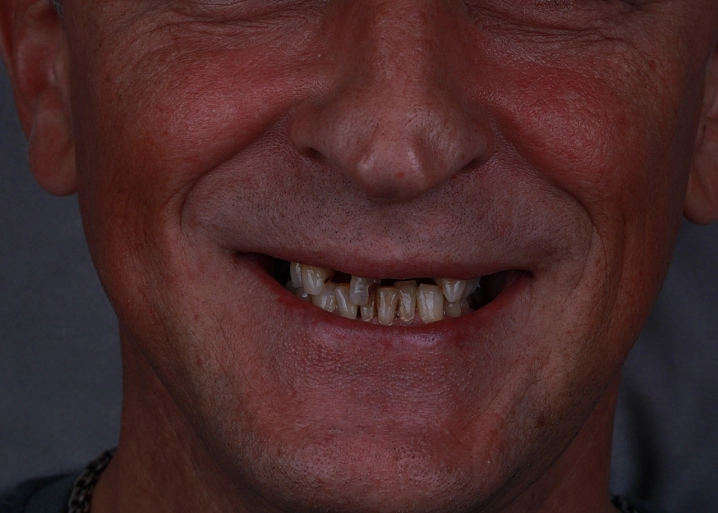

Причины и методы лечения подвижного зуба.